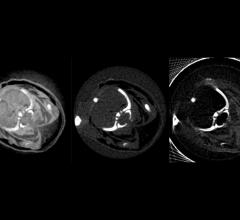

X-ray, or X-radiation, is a form of electromagnetic radiation that can pass through many materials that are opaque to light. They can be used to take images of the inside of the human body.

A standard X-ray provides tremendous value to a clinician for its ability to quickly provide a static image of ...

Musculoskeletal injuries can be difficult to diagnose with a traditional X-ray because X-rays only reveal a static image ...